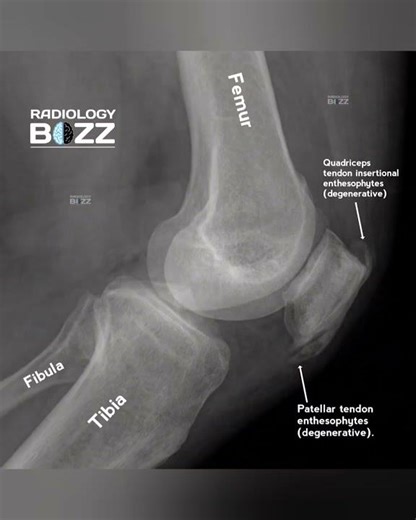

Knee - Enthesopathy

Enthesitis - Osteophytes

- Quadriceps